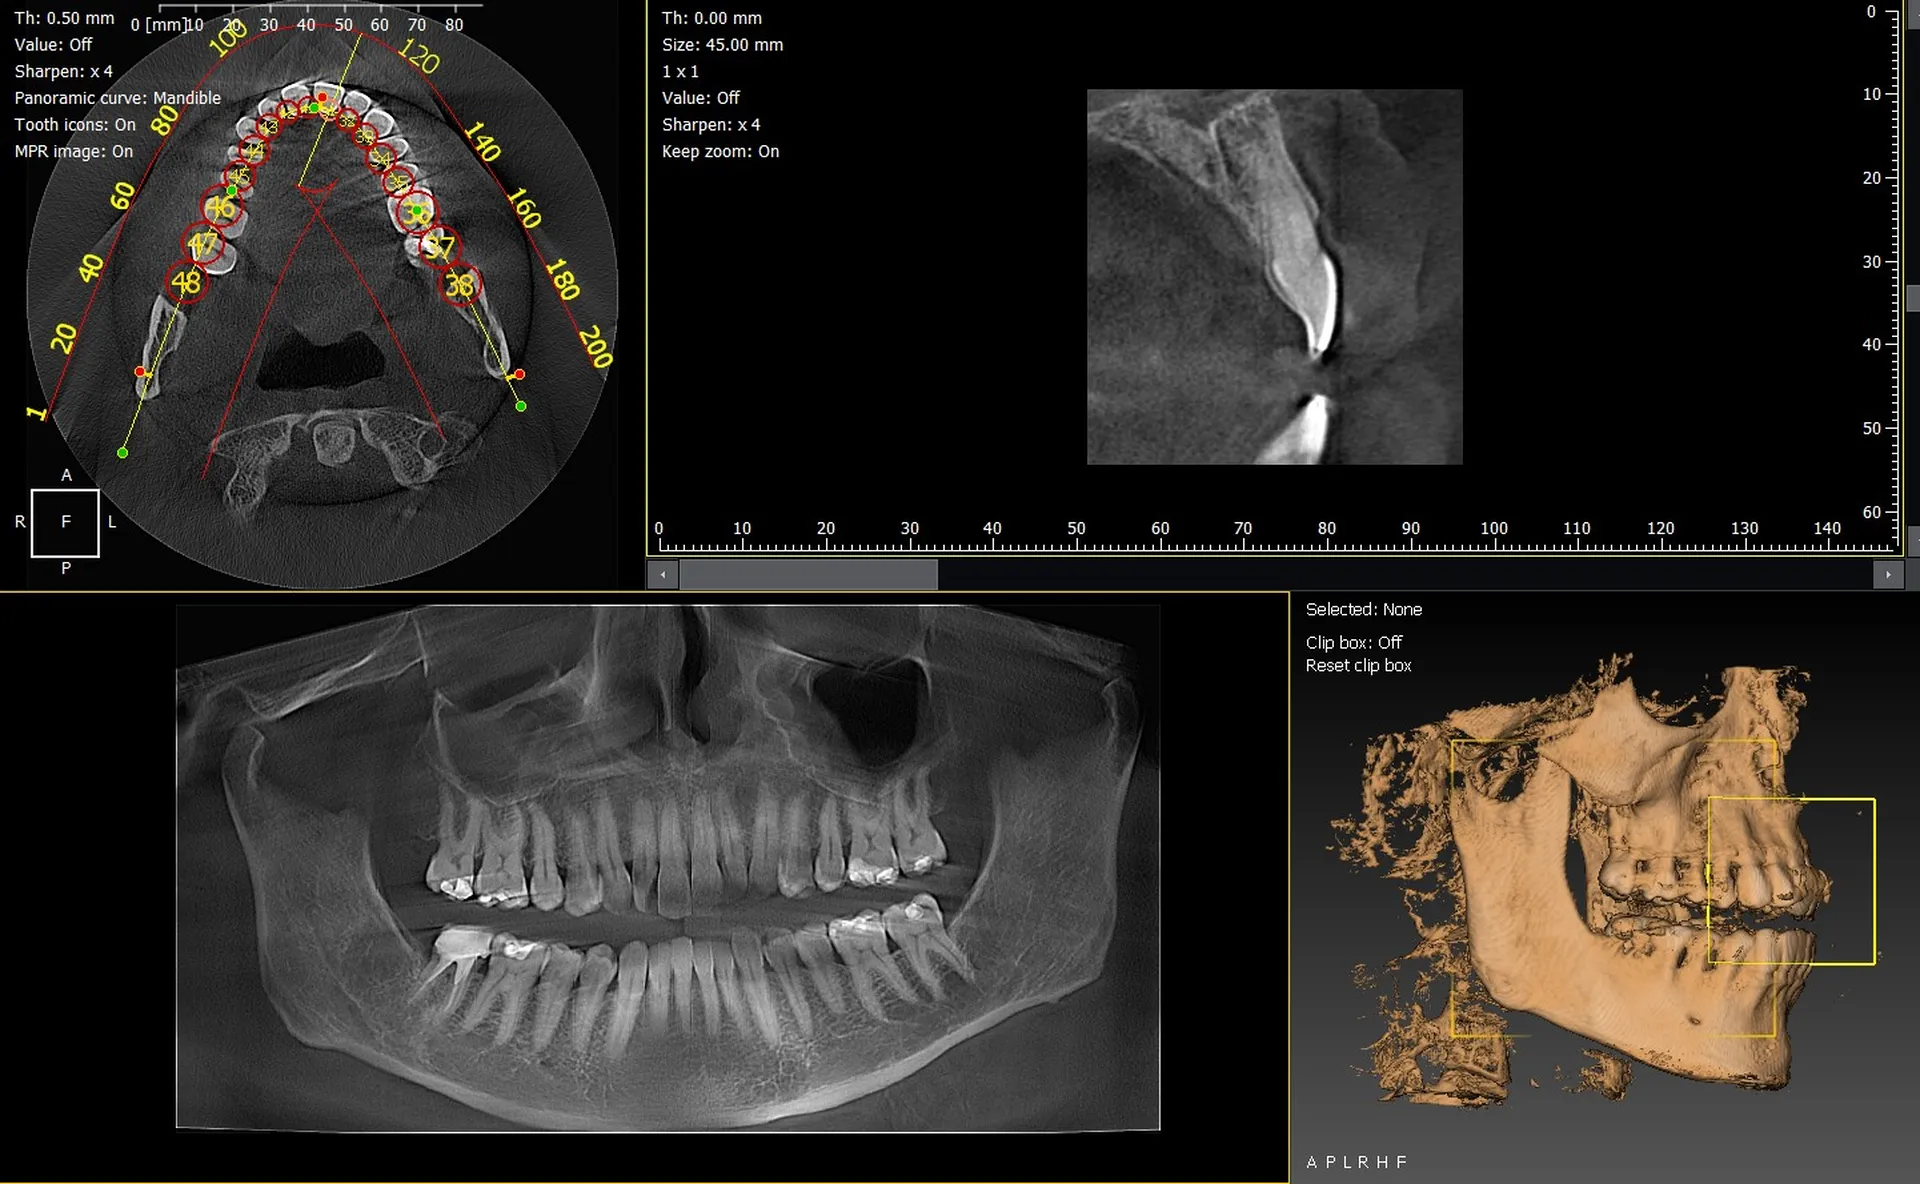

Les cabinets dentaires de Pertuis et du Vaucluse (84) renforcent leur plateau technique grâce à des solutions d’imagerie 3D fiables et performantes. Les panoramiques CBCT 3D VistaVox de Dürr Dental et l’Owandy I-Max 3D comptent parmi les appareils les plus avancés, offrant une excellente qualité d’image et un diagnostic d’une grande précision.

VistaVox 3D : précision et volume optimisé

Le VistaVox se distingue par :

• un volume adapté à la morphologie de l’arcade,

• une haute résolution idéale en implantologie et endodontie,

• une réduction de dose maîtrisée,

• un positionnement simplifié du patient.

Owandy I-Max : compact, intuitif et polyvalent

L’Owandy I-Max 3D séduit grâce à :

• son design mural compact,

• ses protocoles 2D/3D rapides,

• une qualité d’image remarquable,

• une utilisation intuitive.